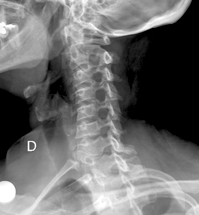

Columna Cervical Oblícua

Se sugiere hacer en posicion de pie, si bien se puede realizar con el paciente en decúbito. Se gira 45 o separando el lado en estudio del cassette radiográfico. El haz de rayos es dirigido a la vértebra C4, con una angulación de 15 o a 20 o hacia cefálico